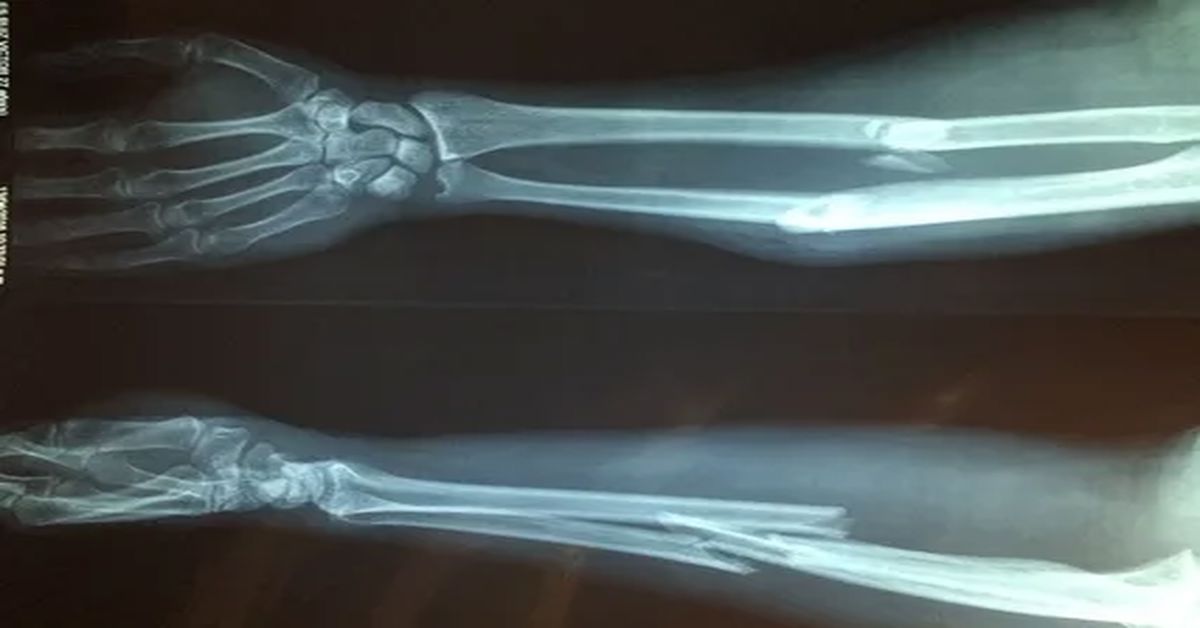

Belirtiler incelendiğinde, Cam kemik hastalığı en sık tekrarlayan kemik kırıkları ile kendini gösterir. Bu kırıklar bazen hafif darbelerle oluşur. Kısa boy, kemik eğrilikleri ve kas zayıflığı da görülebilir. Göz aklarının mavi ya da gri renkte olması ayırt edici bir bulgudur. Bazı bireylerde diş yapısında bozulma ve işitme kaybı da tabloya eşlik edebilir. Belirtiler yaşla birlikte değişkenlik gösterebilir.

Hafif seyreden olgularda kişiler uzun süre tanı almadan yaşayabilir. Kırıklar az sayıda olabilir. Ağır formlarda ise sık kırıklar ve kemik şekil bozuklukları görülür. Bu durum erken tanıyı zorunlu kılar. Düzenli takip süreci önemlidir.

Tedavi sürecinde Cam kemik hastalığı olan bireylerde ortopedik yaklaşımlar önemlidir. Kırıkların doğru şekilde tedavi edilmesi gerekir. Bazı durumlarda cerrahi müdahaleler planlanabilir. Metal destekler ile kemiklerin güçlendirilmesi amaçlanır. Bu işlemler hareket kabiliyetini artırmaya yardımcı olur.